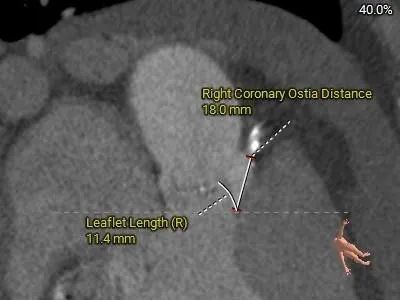

冠脉测量:

冠脉开口高度可,切线角度测量未见冗长瓣叶

•-左、右冠脉开口高度可,左冠起源于STJ之上;切线角度测量未见冗长瓣叶;

•-瓦氏窦、窦管交界内径稍偏小,升主动脉扩张,最宽处约45.2mm;